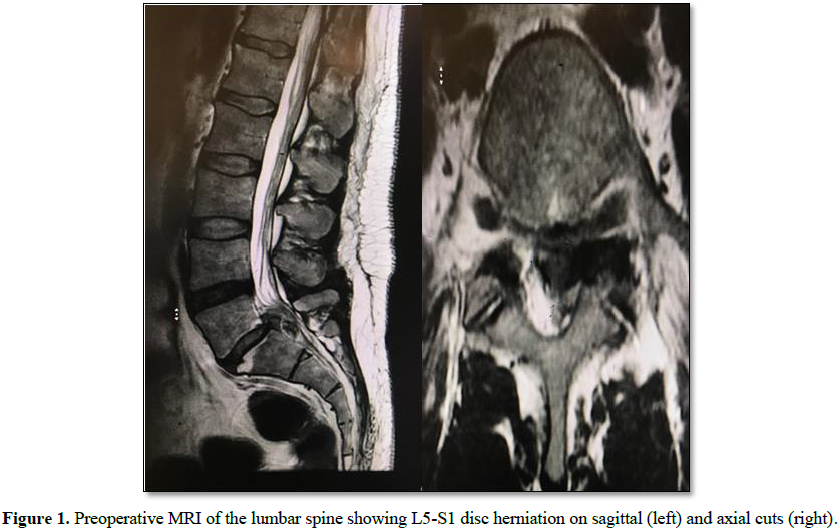

An

incidental dural tear is a well-known complication in both open and

percutaneous lumbar spine surgery. Several techniques have been described for

surgical repair of dural tears in open lumbar spine surgery. However, the

treatment of iatrogenic dural tears in endoscopic spinal surgery remains

challenging. The objective of this report is to describe a technique for

endoscopic dural closure using a collagenous patch derived from bovine

pericardium (Tutopatch) which is simple and effective.

The technique described above is simple

and does not require the use of any suturing materials. It entails the use of

intradural and epidural patch to repair the dural defect (double-layered

duraplasty). Using only an epidural patch will not resist the pressure of a CSF

leak. If an intradural patch is added, then the CSF pressure will push the

patch against the dural wall defect and prevent any CSF leakage or rootlets

herniation. Hence, this method will provide a more watertight dural repair than

a one-layer dural patch. In addition, the collagen matrix initiates clot

formation, resulting in a chemical seal. It also provides a chemical signal for

fibroblasts infiltration which deposit new collagen, thereby reconstituting new

dura.